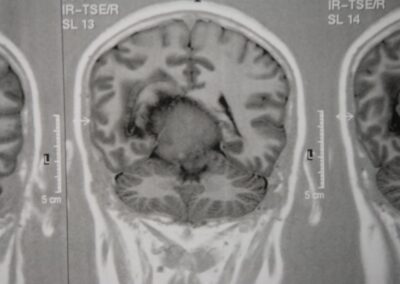

Signos y exámenes

El examen muestra, a menudo, signos neurológicos generales o focales que son específicos del sitio del tumor. Algunos tumores no muestran síntomas hasta que ya son bastante grandes y causan rápido deterioro neurológico, mientras que otros se caracterizan por los síntomas progresivos lentos. La mayoría de los tumores muestra signos típicos de masas que ocupan espacio (lesión ocupante de espacio: LOE), los cuales causan aumento de la presión intracraneal y compresión del tejido cerebral.

El diagnóstico se puede confirmar y el tumor localizar mediante:

• TAC cerebral

• RM cerebral